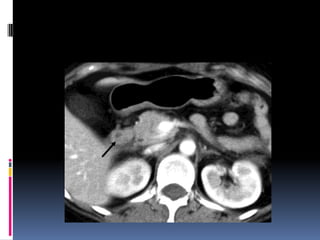

INJURIA PANCREÁTICA  Resultade la compresión de la glándula contra la columna vertebral  Manubrio de bicicleta  Clínica y laboratorio inicialmente inespecíficos

 Signos indirectosde lesión traumática  Agrandamiento difuso  Grasa peripancreática “sucia”  Líquido periglandular  Engrosamiento fascia pararrenal anterior